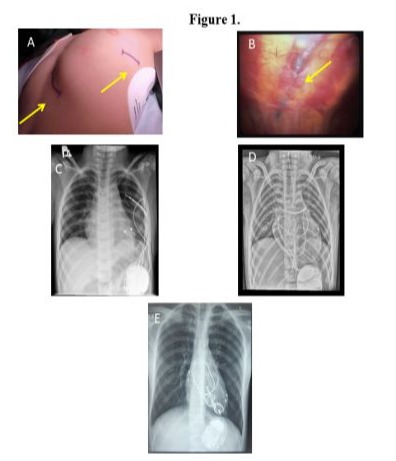

There were no major complications during the procedure or the postoperative period. In 1 patient, operated on at the age of 3 years, we observed displacement of the ICD lead from the sub-pleural channel that was created. The electrode measurements remained unchanged during the follow-up. The patient was operated on 8 years after the first surgery due to damage to the ventricular pacing lead. The surgery was performed via a left anterolateral rethoracotomy. The ventricular pacing lead and the ICD lead were replaced with new ones, a left atrial pacing lead was additionally implanted, and the ICD was changed due to battery depletion. The postoperative course was uneventful (Figure 3 A,B). The youngest patient, who suffered from short QT syndrome, underwent surgery on their 37th day of life. An ICD was placed in the pleural cavity because of the patient’s size (Figure 3C).